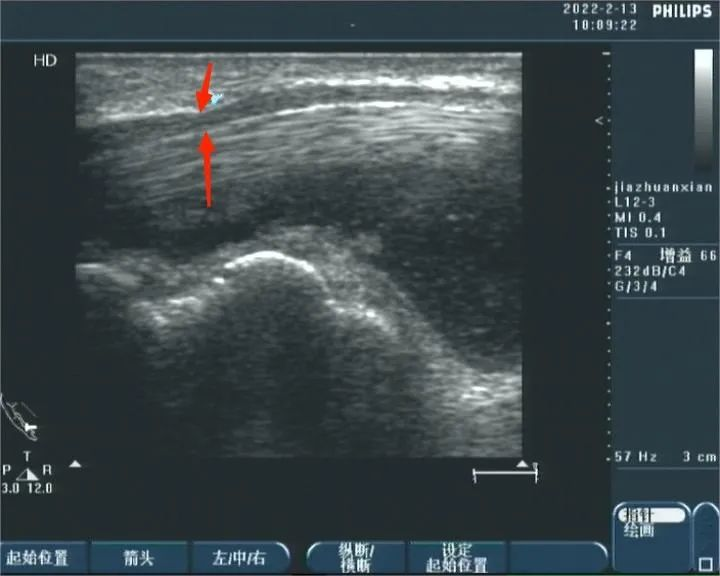

3、肢体麻木、疼痛、乏力等

检查是否存在神经病变,如神经卡压、神经肿瘤等。常见的神经卡压病变包括腕管综合征、肘管综合征、梨状肌综合征、腓神经卡压综合征等;常见的神经肿瘤包括神经鞘瘤、创伤性神经瘤等。

正中神经卡压